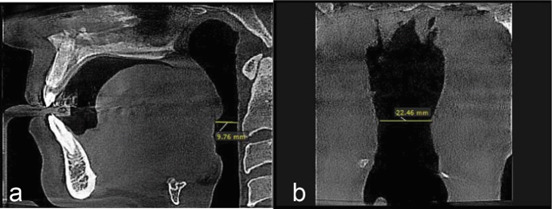

Materials and method: In this retrospective cross-sectional study, cone beam computed tomography (CBCT) records of 100 patients were analyzed. Patients were snoring non-OSA individuals, diagnosed through a thorough examination and negative polysomnography results. CBCT scans were executed in the standard position as per the specified protocol of the Sleep Center. Upper airway was divided into four parts (nasopharynx, velopharynx, oropharynx, and hypopharynx), and anteroposterior (AP) and transverse (T) dimensions within the minimal cross-sectional area of each respective region were evaluated. BMI, upper airway dimension, and hyoid bone were analyzed using Pearson and Spearman's correlation tests.

Results:  The retrognathion-hyoid-4th cervical vertebra (RHV) angle representative of the hyoid position was significantly greater in females (p Value=0.000). It also statistically decreased significantly in snorers aged 36-50 and 51-65, p= 0.006 and 0.012, respectively. Snorers had above-average BMI in all age groups and both genders. The AP-hypopharynx significantly correlated with BMI (p= 0.022).

Conclusion:  The hyoid position was gender-dependent, with a superior position in females. It was also age-dependent, with a more inferior position in snorers aged 36-65 compared to younger ages (20-35). The AP-velopharynx is a constriction region in the airway of snorers. Snorers were overweight in all age groups and both genders. BMI had a significant correlation with the AP-hypopharynx.